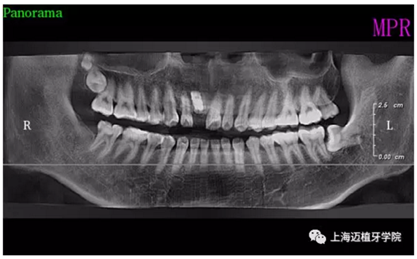

術(shù)前全景片

術(shù)后全景片